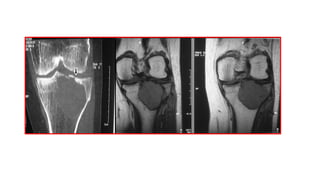

OSTEOMAOSTEOIDE NIÑO 11A.: gonalgia

derecha de larga evolución.Epífisis tibial

proximalderecha, opacidadcentral. Abajo

derecha: corte transversal de TAC.

Nidus calcificado.

OSTEOMA OSTEOIDE NIÑO 12A.: bultoma

pierna derecha. Engrosamiento focal y

esclerosis cortical medial diáfisis tibial

derecha regular.

Abajo derecha: corte transversal de TAC.

Pequeña imagen lítica de aprox. 0.5 cm de

diámetro.

Nidus sin calcificar